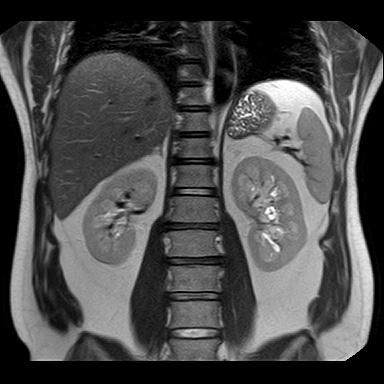

신장 양쪽에 혹이 있다고 하는데 (좌신, 등)

• 4번 째 사진

• 비뇨기과를 가시는 것이 맞고, 제공해주신 MRI와 초음파 소견을 종합하면, 양측 신장에 병변이 보이기는 하나 형태가 서로 다릅니다. 한쪽은 비교적 경계가 명확하고 밝게 보이는 병변으로 낭종 가능성이 우선 고려되고, 반대쪽은 내부 신호가 혼재된 형태로 단순 낭종 외의 병변 가능성도 완전히 배제하기는 어렵습니다. 다만 단일 컷 이미지로는 조영 증강 여부, 내부 구조, 혈류 평가가 제한되어 확정 판단은 불가능합니다.

임상적으로 중요한 기준은 단순 낭종인지, 복합 낭종인지, 혹은 고형 종양인지 구분하는 것입니다. 단순 낭종이면 추가 치료 없이 경과관찰이 원칙이고, 복합 낭종이나 고형 병변이면 추가 평가가 필요합니다. 이 구분은 조영증강 CT 또는 조영 MRI에서 보스니악 분류 기준으로 판단합니다.

진료과 선택은 비뇨기과가 우선입니다. 신장 종양 및 낭종의 1차 평가와 추적, 필요 시 수술까지 담당하는 과입니다. 영상의학과는 판독을 담당하는 과로 직접 진료는 하지 않으며, 신장내과는 기능 이상이나 만성신질환이 있을 때 적합합니다.

권장 흐름은 다음과 같습니다. 현재 MRI 원본과 판독지 확보 → 비뇨기과 방문 → 필요 시 조영 CT 또는 조영 MRI 추가 (만약 수술적 치료를 계획한다면 신혈관 파악이 용이한 3D renal angio CT 등 추가 촬영할 수도 있습니다.)→ 보스니악 분류에 따른 추적 또는 치료 결정입니다.

현 시점에서 급하게 의심할 소견으로 단정하기는 어렵지만, 양측성 병변이므로 단순 낭종인지 확인은 반드시 필요합니다. 특히 40대에서는 우연히 발견되는 낭종이 흔하지만, 복합 낭종은 일부에서 종양과 연관될 수 있어 정밀평가가 필요합니다.